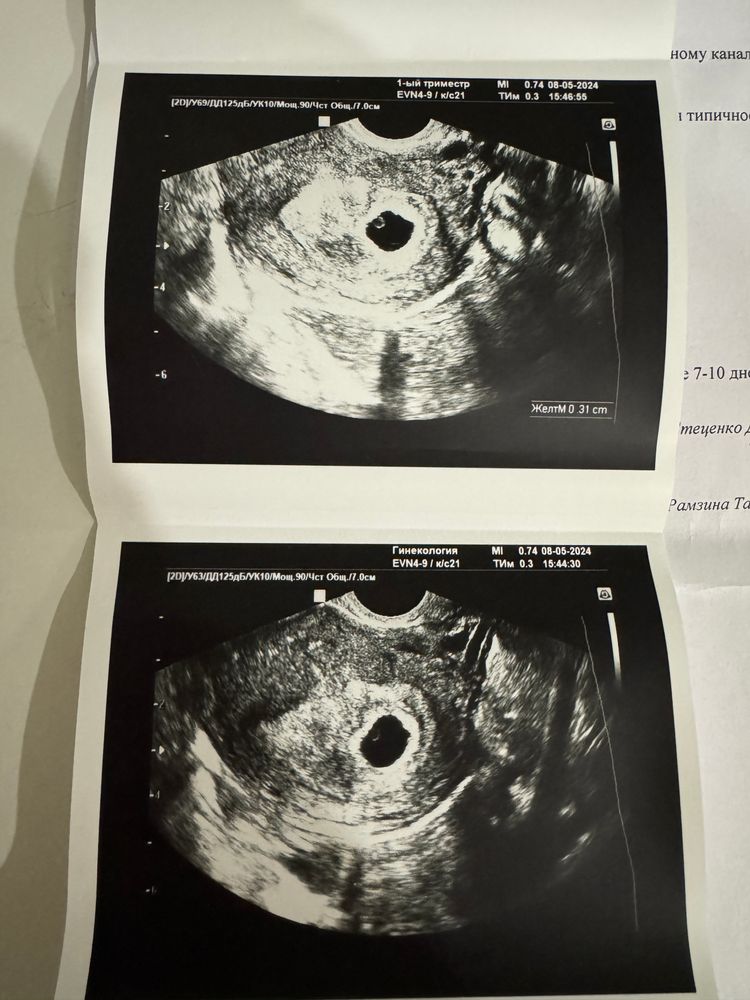

Первое узи 4 недели и 5 дней . Вопросов стало ещё больше 😅

Марина, прикрепила к теме , именно 2,8 см 🫣 Поэтому врач так и удивилась и сидела мне на картинках показывала у тебя должно быть «так» , а у тебя уже «вот так» это больше твоего срока . Но сроки я все описала

Я делала первое узи на сроке 5-6 недель, пя 7,8 мм, жт 1,8 мм. Думаю узистка не правильно посчитала, ваши размеры как раз на срок 4-5

Альбишка, на 6 неделях размеры были пя 13, жм 4 мм

Альбишка, у меня 28мм ПЯ почти в 3 раза больше вашего на 6 неделях 🙈 вот поэтому и столько вопросов 😅 вообщем жду 25 мая , пойду к моей она там всё как надо посмотрит 😁

Не может быть такое пя с вашим хгч,у меня на 20 дпо хгч 7200 был,УЗИ 22 дпо пя 8 мм,жм 1,6,на 27 дпо хгч 38500,УЗИ 31 дпо пя 19,ктр 5,4 и сб + от уровня хгч зависит размер пя,при 8 тысячах никак не может быть пя 2,8 см

Дарья , у вас отличное пя для срока,но не 28

Вот мое пя 28 мм Изображение У вас ошибка с размерами,на фото пя не 2,8 см,а меньше

Может быть ПЯ у вас все таки 2,8 мм?😊. При 28 мм должен давно быть эмбрион и не маленький. У меня в 6,3 было ПЯ 20 мм всего и эмбрион с сердцебиением. Скорее всего узистка в описании напутала и вместо мм написала см. Все у вас по сроку.